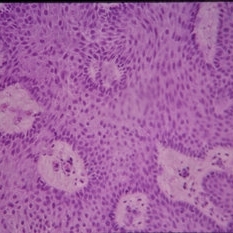

Histopathology of Linear Sebaceous Nevus Syndrome

Histopathology of Linear Sebaceous Nevus Syndrome

Feb 20 2015 by H. Michael Lambert, MD

Histopathology of linear sebaceous nevus syndrome.

Condition/keywords: histopathology, linear nevus sebaceous syndrome